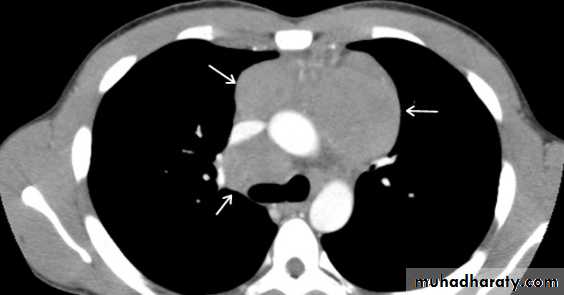

posterior divisions for descriptive purposes. This can be demonstrated on a lateral CXR , but is usually performed with CT.CT and MRI of normal mediastinum: Computed tomography is the standard method for imaging the mediastinum. MRI is used only occasionally. The cross sectional display and the ability to distinguish between fat, various soft tissues and blood vessels are major advantages of both techniques.

• The mediastinum is composed predominantly of blood vessels. Visualization and differentiation from other soft tissue structures is aided with the use of intravenous contrast medium. At MRI, the larger vessels are readily seen

without contrast agent.

• The only other normal structures of appreciable size are the thymus, oesophagus, trachea and bronchi.

• Normal lymph nodes are small, usually less than 6 mm in diameter (maximum 10 mm), and many are not visible.

• The mediastinal structures are surrounded by fat (low density on CT), this enables visualization of other small soft tissue masses which are generally of increased density.

CT scan : Computed tomography provides much more information than CXRs.

There are two main advantages of CT.

1 -Abnormalities can be accurately localized: Knowledge of the precise shape, position and size of a mediastinal mass frequently narrows the differential diagnosis. For instance, contiguity of the mass with the thyroid in the neck suggests a goitre , and multiple oval-shaped masses suggest lymphadenopathy

2- Occasionally, the density of the abnormality reveals it nature:

• Because of its high iodine content, thyroid tissue is of higher attenuation than muscle prior to contrast medium administration. After contrast, it enhances brightly.

• Intravenous contrast enhancement permits delineation of aneurysms and anomalous blood vessels from other masses.

• Calcification is readily seen. The presence of calcification in a mass is frequently seen in benign conditions.

• Cysts containing clear fluid, e.g. pericardial cysts and some bronchogenic cysts can be recognized by a CT number close to water (0 Hounsfield units).